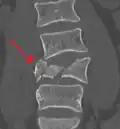

A burst fracture of L4 as seen on CT